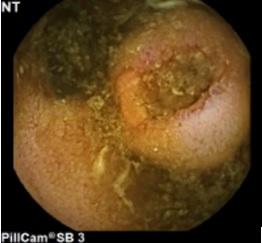

潰瘍形成した小腸粘膜下腫瘍

小腸内視鏡検査

当院では主にカプセル内視鏡で発見された出血源や腫瘍に対しての止血処置・精査として行っております。小腸内視鏡を常備している施設は決して多いとは言えず、近隣施設からも小腸の精査目的に多数のご紹介を頂いております。